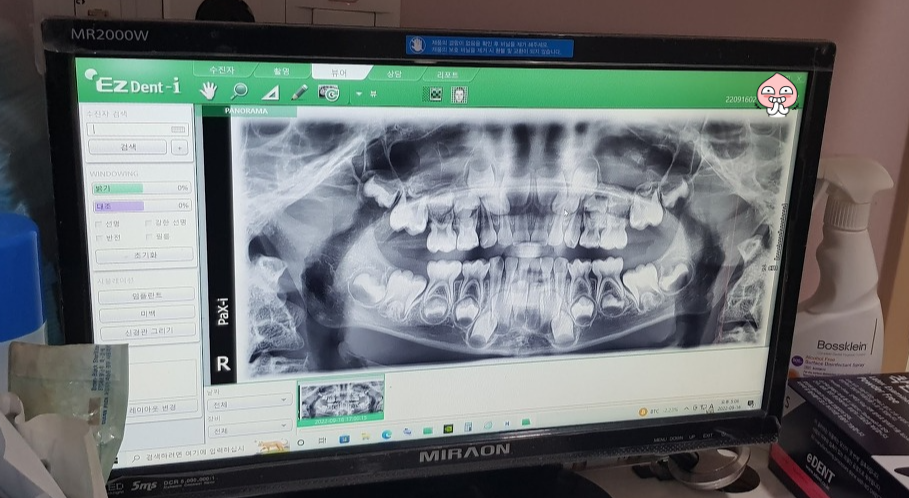

사진을 찍었습니다.

이 사진을 보시더니 5개는 신경치료를 하고 은으로 씌워야 하고 3개는 떼우는 치료를 해야 한다고 하셨습니다.

신경치료는 신경을 죽이는 치료지만 영구치가 나오는데 아무런 문제가 없다고 하셨습니다.

그리고 누운 상태에서 바로 사진을 찍었습니다. 사진상으로 보니 오른쪽 위 어금니가 썩어서 푹 파여 있네요. 그리고 붙어있는 어금니도 같이 썩은 것 같습니다.

이 어금니는 신경치료를 해야하구요. 사진상으로 잘 안보이지만 붙어 있는 어금니도 신경치료를 해야할 것 같습니다. 그리고 은으로 씌울 겁니다. 만약 붙어있는 어금니가 신경치료 안해도 될 정도면 그냥 떼울겁니다.